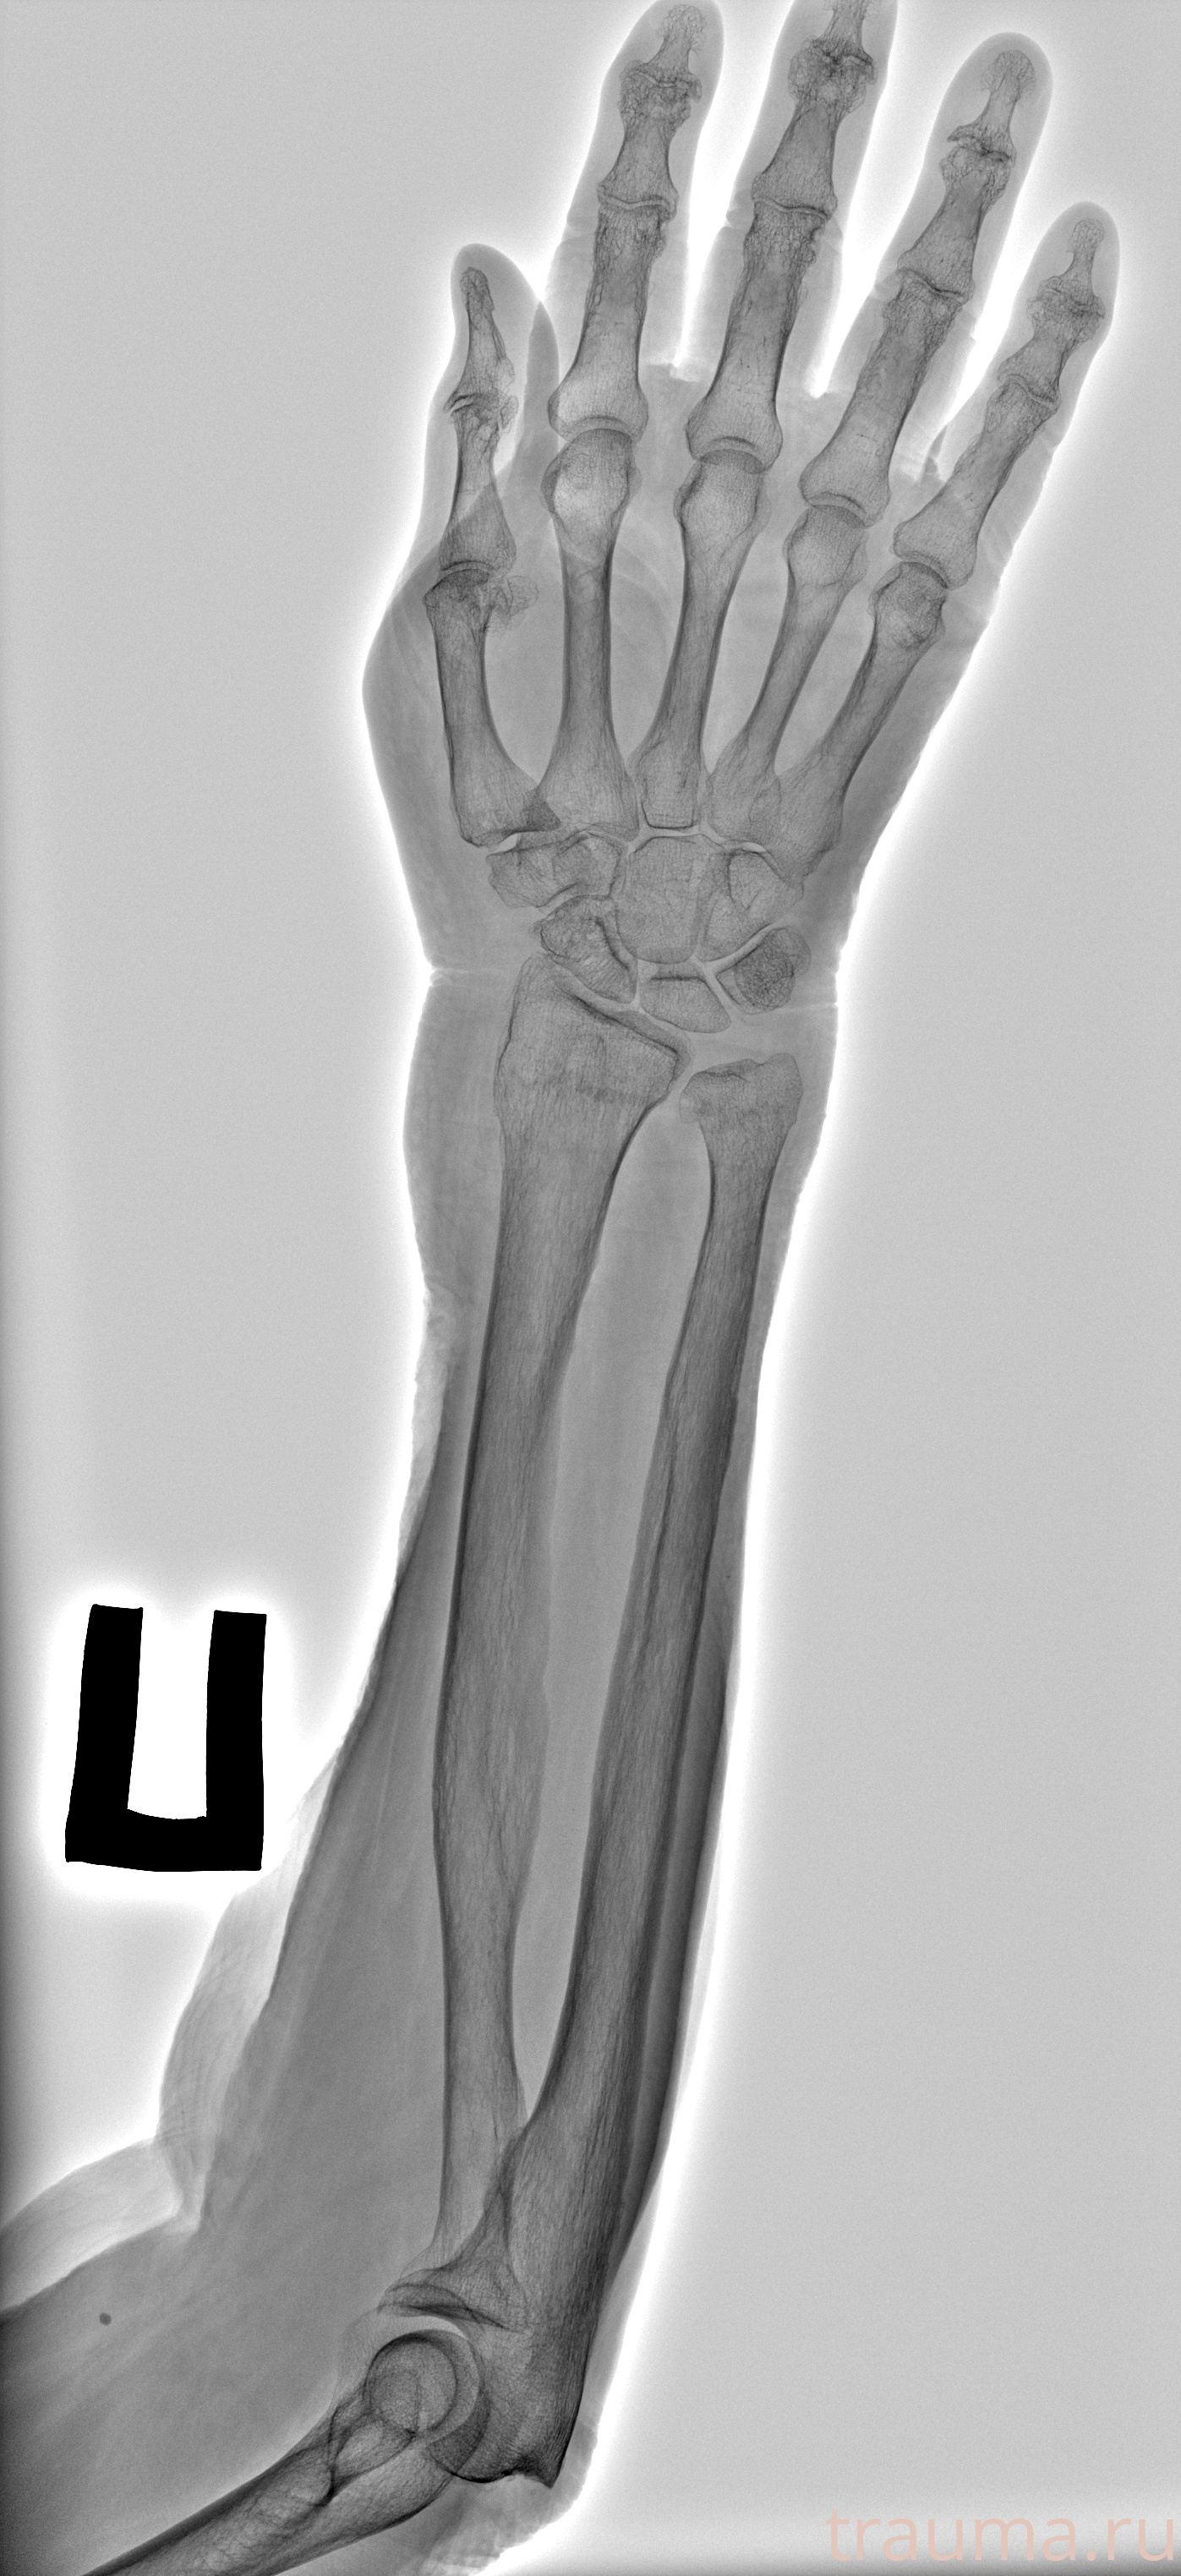

Перелом 3-5 ребер слева